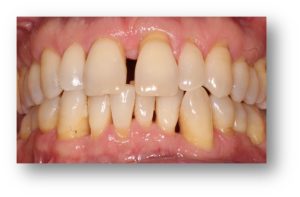

![]() | ![]() |

| Untreated severe gum disease | Gum disease treated and stabilised by Dr Halai |